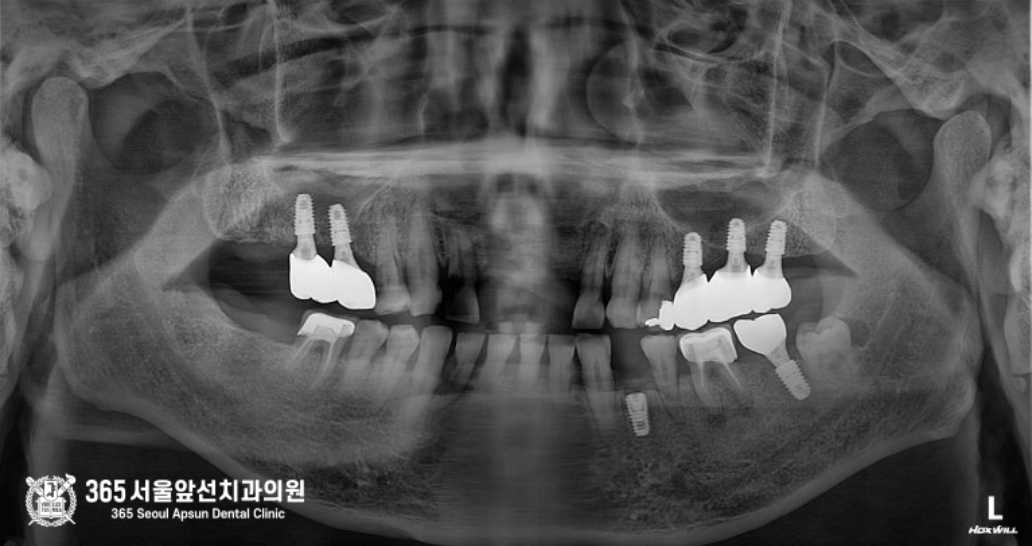

3차원 CT 영상 소견입니다. 구강내 기준으로 오른쪽 앞니 상방으로 과잉치아가 보이며, 과잉치아 주변에 매우 큰 낭종이 있습니다. 인접한 다른 치아의 입천장쪽으로도 과잉치가 매복되어 있으며, 다행히 해당치아는 낭종을 형성하지는 않았던 상태입니다. 촬영일시 : 2024.05.02. 정면 ct 사진입니다. 코 아래쪽으로 2개의 과잉치아가 매복되어 있으며 매우 큰 낭종도 보입니다. 2개의 매복과잉치와 코 아래의 낭종을 동시에 제거하는 수술과 동시에, 왼쪽 아래턱에 심하게 충치가 진행된 치아를 발치하고 임플란트를 식립하는 수술까지 진행했으며 수술시간은 총 36분에 걸쳐서 순조롭게 진행되었습니다 ㅎㅎ 촬영일시 : 2024.05.02. 과잉치 발치와 낭종 적출술을 동시에 진행하고 있는 모습이며, 가장 오른쪽 사진은 적출된 낭종과 과잉치입니다. 낭종과 심하게 진행된 치주염으로 인해 앞니 두개 치아는 발치를 해야하는 상황이었으며, 낭종 제거 후 6개월 이상 기다렸다가 뼈의 회복이 진행되면 임플란트 식립을 하기로 했습니다 ㅎㅎ 촬영일시 : 2024.12.10. 아래쪽 임플란트 수술까지 합쳐서 총 36분에 걸쳐서 순조롭게 진행되었으며, 환자분께서도 만족하셨던 증례입니다. 촬영일시 : 2025.02.14. 대략 6개월 후 보철까지 모두 완료된 엑스레이 사진입니다. 아무리 복잡하고 어려운 치료라도 자신있습니다. ㅎㅎ 부담갖지 마시고 내원해주시면 최선을 다해 치료하겠습니다. 오늘은 도화동치과 365서울앞선치과에서 매복된 과잉치와 그로인해 생긴 낭종을 제거한 증례를 소개해드렸습니다. 앞으로도 좋은 치료 증례로 찾아뵙겠습니다 ! [ 치료기간: 2024년 5월2일 ~ 2025년 2월 14일 ] ※ 365서울앞선치과의원의 모든 포스팅은 각 진료과 의료진이 직접 작성합니다. 365서울앞선치과의원 블로그의 임상 케이스 게시물은 환자분께 의학적으로 정확하고 상세한 정보를 드리기 위해 각 진료과 의료진이 직접 작성하며, 모든 증례 사진은 본원 의료진이 직접 시술한 증례를 촬영한 것으로, 의료법 제23조, 제56조에 의거하며 환자분의 동의를 얻어 포스팅에 사용하였습니다. 또한 해당 케이스는 본 환자분의 치료 결과이며, 환자 상태에 따라 치료의 결과는 달라질 수 있습니다. |